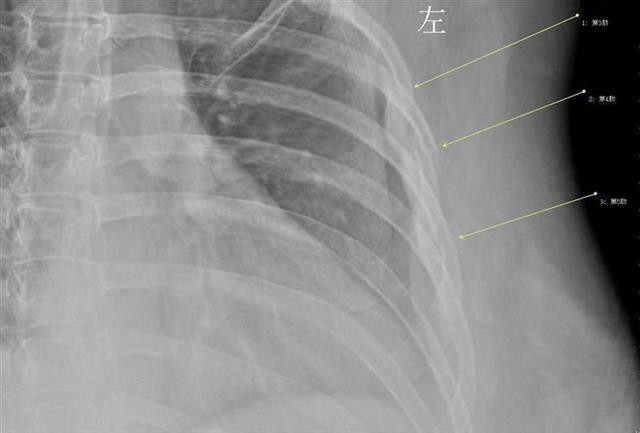

Sáng hôm sau, cô đến Bệnh viện Trung ương Vũ Hán để kiểm tra và bác sĩ đã chụp X-quang một số vùng cơ thể để tìm ra nguyên nhân của cơn đau. Và rồi bác sĩ đã rất ngạc nhiên khi phát hiện ra rằng chiếc xương sườn thứ 3, thứ 4 và thứ 5 của cô đã bị gãy do cơn ho dữ dội.

Bác sĩ đã thực hiện một số xét nghiệm mật độ xương cho Tiểu Hán và thấy rằng xương của cô giống với người ở độ tuổi 60 và cô đang trên đường bị loãng xương sớm .